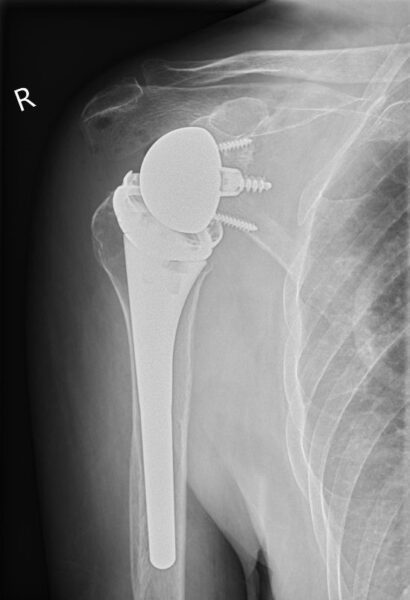

Omgekeerde schouderprothese

Een omgekeerde schouderprothese heet ook wel een reversed schouderprothese. Een omgekeerde schouderprothese is een mogelijkheid als de pezen in de schouder onherstelbaar gescheurd zijn en de spieren rondom de schouder niet meer goed werken. Bij deze prothese komt de schouderkop op de plaats van de kom en de kom op de plaats van de schouderkop. Daardoor komt het draaipunt van de schouder anders te liggen. U kunt de arm dan beter bewegen, terwijl u minder spieren gebruikt.